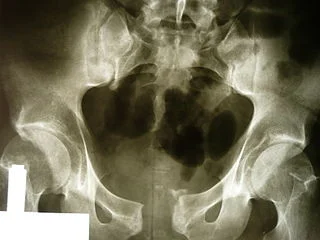

You finish checking the aircraft with the flight nurse and sit down to begin the 20:30 brief with the flight crew when the tones drop and you are dispatched for your first flight of the evening, a scene flight to Franklin County, Indiana for an “un-helmeted motorcyclist”. You grab the blood cooler, perform a safety walk-around the aircraft and strap yourself in back